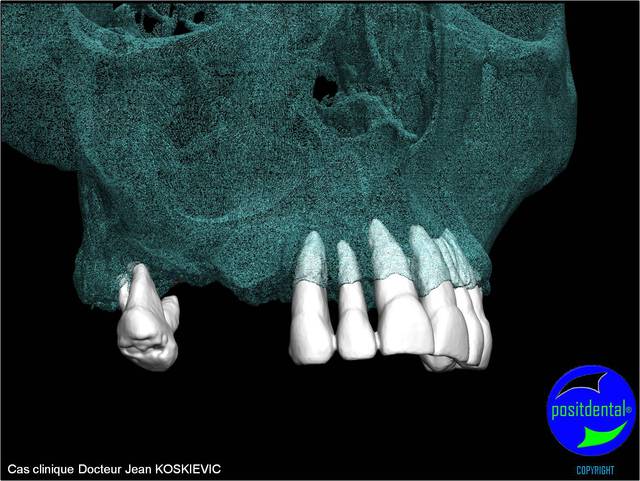

rendu 3D maxillaire sup, pano et photo

3D maxillaire inférieur et photo

et la projet 10 implants maxillaire sup